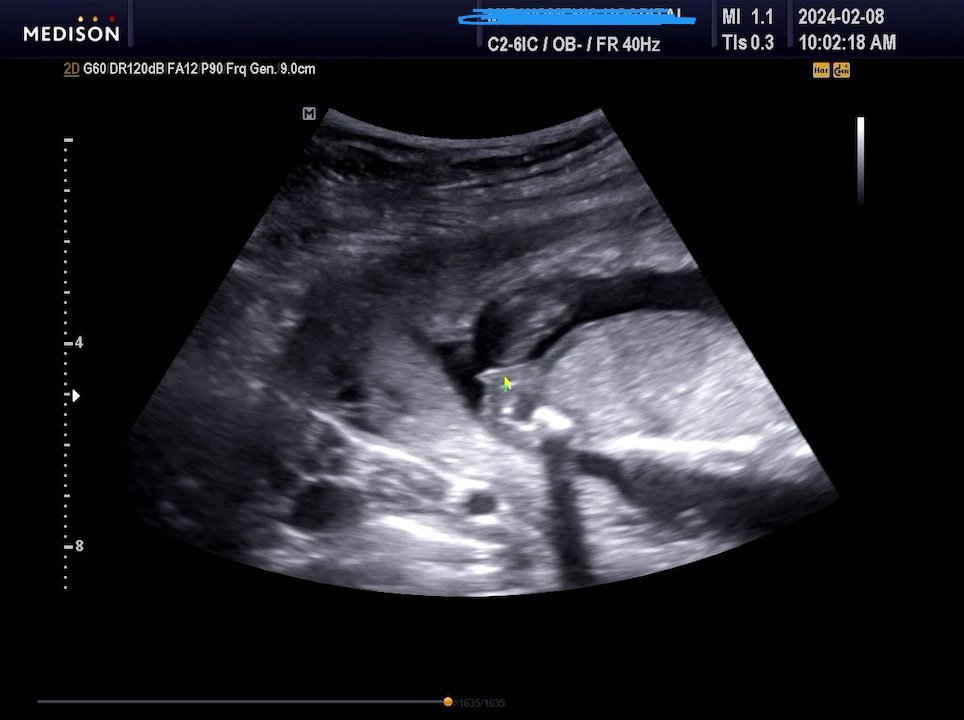

계획임신은 아니었던 셋째 아들이 둘이라 내심 딸을 기대하긴 했는데, 아니요 사실은 딸이어야만 했죠..제발😭😭 이번 명절 마음을 편하게 보내고 싶어 15주차에 아가 보러 다녀왔는데 의사샘이 덤덤하게 딸이라고 하시네요 😍😍😍 이정도면 자식농사 성공 한거죠? 넘나 행복합니다 ☺️☺️ 남편한테 맞춰보라고 동영상만 띡 던져줬는데 아들이라며 대성통곡 하길래 딸이라고 알려줬더니 너무 좋아하네요 😁😁 남편이 오해한 촘파사진올려요 혹시나 성별 판독에 도움이 되길 바라면서요. 이랬는데 다음번에 갔는데 아들이면 울면서 다시 글 남길게요 😂근데 경험상 두 아들들은 15주전에 존재감이 퐉 나와서 확실히 다른거 같긴해요 ^^;; 이기쁨 아직 가족들과 나누지 못해서 베동에 남겨봐요 명절에가서 써프라이즈 할거에요 🙂 즐거운 명절 맛있는거 드시고 가족들과 행복한 시간 보내세요 🫶🫶 + 시아버지가 막내도 아들이면 아빠집에 오지 말라고 하셨는데 딸이라 가야겠네요 🤣🤣